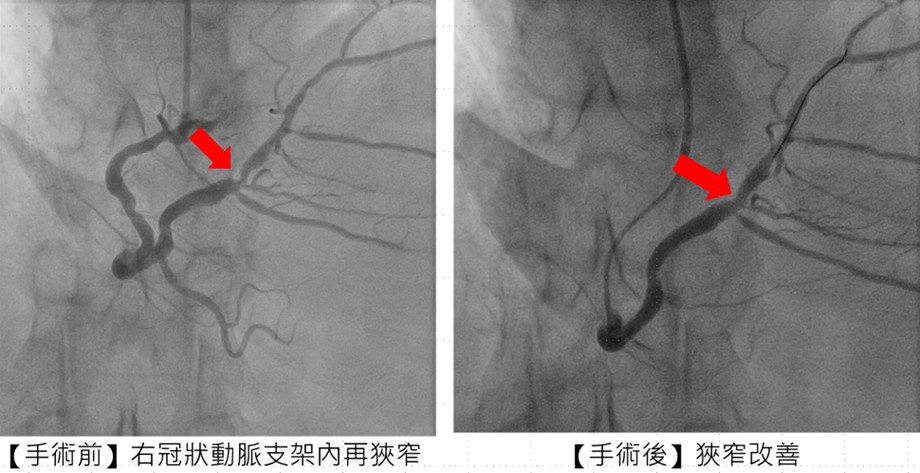

副院長兼心臟科專家陳建鈞醫師進一步說明,張先生病史複雜,支架多次再阻塞,加上長途奔波與壓力,風險極高。團隊經縝密評估,採用「刀片氣球」及「塗藥氣球」治療,不僅打通血管阻塞,也降低再度狹窄的機率,大幅縮短康復時間。手術全程順利,患者隔日即可出院。

圖:治療前與治療後,施行「刀片氣球」及「塗藥氣球」治療後,右冠狀動脈支架狹窄改善(市立醫院公關提供)張先生提到,此次在臺中市立老人復健綜合醫院就醫,除醫療設備先進外,更感動於醫護能以客語溝通,讓身在異鄉的他倍感溫暖。術後生活品質顯著提升,他承諾努力戒菸,維持健康,期許自己能投入更多公益。